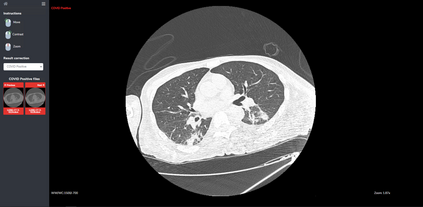

COVID-19 infection caused by SARS-CoV-2 pathogen is a catastrophic pandemic outbreak all over the world with exponential increasing of confirmed cases and, unfortunately, deaths. In this work we propose an AI-powered pipeline, based on the deep-learning paradigm, for automated COVID-19 detection and lesion categorization from CT scans. We first propose a new segmentation module aimed at identifying automatically lung parenchyma and lobes. Next, we combined such segmentation network with classification networks for COVID-19 identification and lesion categorization. We compare the obtained classification results with those obtained by three expert radiologists on a dataset consisting of 162 CT scans. Results showed a sensitivity of 90\% and a specificity of 93.5% for COVID-19 detection, outperforming those yielded by the expert radiologists, and an average lesion categorization accuracy of over 84%. Results also show that a significant role is played by prior lung and lobe segmentation that allowed us to enhance performance by over 20 percent points. The interpretation of the trained AI models, moreover, reveals that the most significant areas for supporting the decision on COVID-19 identification are consistent with the lesions clinically associated to the virus, i.e., crazy paving, consolidation and ground glass. This means that the artificial models are able to discriminate a positive patient from a negative one (both controls and patients with interstitial pneumonia tested negative to COVID) by evaluating the presence of those lesions into CT scans. Finally, the AI models are integrated into a user-friendly GUI to support AI explainability for radiologists, which is publicly available at http://perceivelab.com/covid-ai.